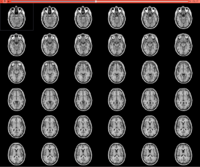

DICOM

• The DICOM and Slicer tutorial provides an introduction to the DICOM standard and shows how to load and visualize DICOM datasets in 3D Slicer version 5.0.

• Author: Sonia Pujol, Ph.D.

• Modules: DICOM, Volumes

• Based on: 3D Slicer version 5.0/4.11

• The 3D Slicer DICOM Tutorial Data contains a torso-CT and a breast MRI.

• The 3D Visualization of DICOM images course guides through 3D data loading and visualization of DICOM images for Radiology Applications in Slicer4.

• Author: Sonia Pujol, Ph.D., Kitt Shaffer, M.D., Ph.D., Ron Kikinis, M.D.

• Audience: Radiologists and users of Slicer who need a more comprehensive overview over Slicer4 visualization capabilities.

• Modules: DICOM, Volumes, Volume Rendering, Models.

• Based on: 3D Slicer version 4.8

• Compatible with 3D Slicer version 4.10

• The 3DVisualizationDICOM_part1 and 3DVisualizationDICOM_part2 datasets contain a series of MR and CT scans, and 3D models of the brain, lung and liver.